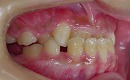

治療前 治療後

近年、反対咬合の治療の選択肢として、

外科矯正(骨切り)が注目されています。

当矯正歯科医院では、体の健康と機能向上の目標に、

歯を抜かず、骨を切らずに治療していく事 を心がけて

日々研鑽しています。

今回も治療には、独自の方法とビムラー装置等を利用して改善しました。

また、咬合バランスを改善する為には、

顎骨の前後のバランス改善だけでは不十分と考え、

かみ合わせの高さなど立体的に改善していく事を心がけています。